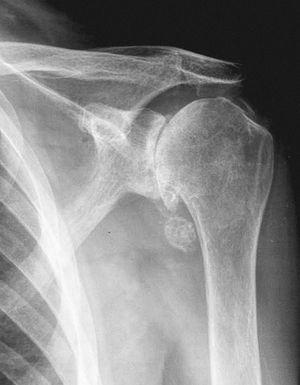

Las exploraciones complementarias mostraron un hemograma y bioquímica normales con calcio, fósforo y uricemia dentro de los límites de la normalidad. La velocidad de sedimentación globular y la proteína C reactiva fueron normales y el factor reumatoide negativo. La radiología (Rx) objetivó signos degenerativos en las articulaciones fémoro-tibiales con la presencia de calcificaciones meniscales (fig. 1); la Rx de manos mostró calcificación de ligamento triangular del carpo y signos degenerativos de interfalángicas proximales y distales. La Rx del hombro (fig. 2) izquierdo mostró fragmentos osteocondrales, excrecencias óseas en articulación escápulo-humeral con signos degenerativos y calcificaciones. El líquido articular de la rodilla izquierda fue de características mecánicas, con presencia de cristales de pirofosfato cálcico dihidratado al visualizarlo por microscopio de luz polarizada; los cultivos fueron negativos.

Figura 2. Radiografía póstero-anterior (P-A) hombro izquierdo. Disminución espacio gleno-humeral, esclerosis subcondral, fragmento osteocondral y calcificaciones.